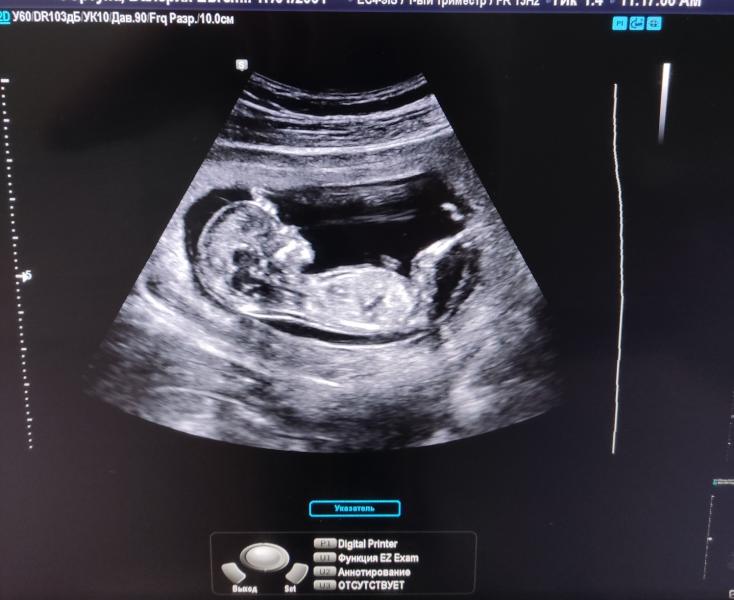

Ну что, первый скрининг пройден🙏🏼🎉

Теперь не терпится узнать пол😁

Сегодня тоже скриннинг прошла. Про пол сказали ещё рано и тоже хочется узнать , когда идти можно.